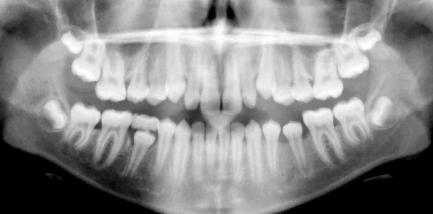

2.) Das Orthopantomogramm (OPG) oder auch Panorama-Übersichtsaufnahme zeigt den Stand des Zahnwechsels, die Zahnanlagen im Kiefer, Fehlbildungen der Zähne, den Zustand der Zahnwurzeln und des Zahnhalteapparates (Parodont).

Insbesondere beim Wechselgebiss gibt das Röntgenbild dem Zahnarzt und Kieferorthopäden die erforderlichen Informationen über die Anlage und Lage von Zähnen sowie den Entwicklungsstand der Wurzelbildung. Hier können auch rechtzeitig besondere Befunde wie Nichtanlage von Zähnen, überzählige Zähne und falsch liegende Zähne (Retentionen) entdeckt werden.

Diese Aufnahmen werden während der Behandlung wiederholt, um z.B. den Zahnwechsel zu kontrollieren, die Zahnachsenstellung zu überprüfen und Veränderungen am Zahnhalteapparat und der Zahnwurzel zu sehen.

Spätes Wechselgebiss